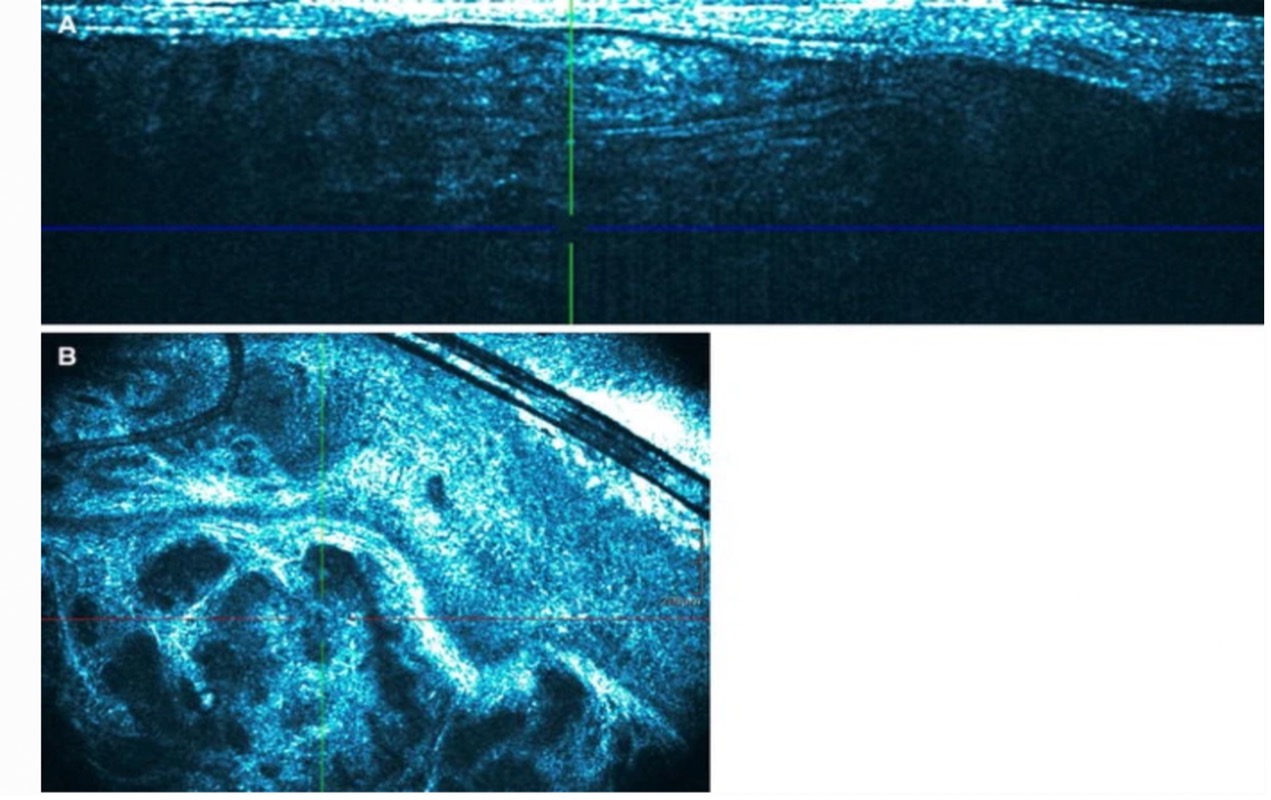

来源于:本站诊断非黑色素瘤细胞癌中基底细胞癌(BCC)的方法——光学相干断层扫描

基底细胞癌(BCC)是高加索人最常见的癌症类型,全球发病率不断上升。其患病概率与紫外线暴露密切相关,肿瘤通常发生在皮肤的显眼部位。 光学相干断层扫描(OCT)是一种基于干涉测量原理的非侵入性光学成像技术,提供适合皮肤图案识别的微米分辨率图像。OCT一直被用于眼科进行视网膜成像,自20世纪... -